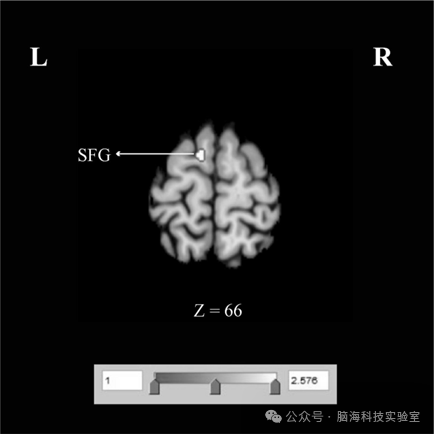

在脑活动增强差异的对比分析中发现,与 ID 患者相比,GAD 患者在左侧额上回(superior frontal gyrusSFG)表现出更显著的脑活动增强(见表 3、图 3)。

除功能活动的共性模式外,本研究还揭示了IDGAD之间的功能活动差异。与ID患者相比,GAD患者在左侧额上回(superior frontal gyrusSFG)表现出更显著的脑活动增强。大量fMRI研究表明,SFG背外侧前额叶皮层(dorsolateral prefrontal cortexDLPFC)的重要组成部分,而该脑区已被证实与焦虑和抑郁密切相关。SFG活动的增强可能导致GAD患者在执行功能、情绪调节及社会功能方面出现功能障碍。因此,本研究推测,左侧SFGIDGAD患者之间的功能差异,可能构成两种障碍临床表现不同的神经影像学基础

本研究识别出IDGAD在默认模式网络相关脑区中的一致性功能活动改变,主要涉及左侧后扣带回(posterior cingulate cortexPCC)、左侧楔前叶(precuneus)及左侧内侧前额叶皮层(medial prefrontal cortexmPFC,提示上述脑区可能构成ID GAD共同神经通路。此外,本研究还发现IDGAD 在左侧额上回(superior frontal gyrusSFG)存在差异性激活模式,表明两种障碍可能具有特异性的神经机制。这些发现为未来临床干预与治疗策略的制定提供了潜在的参考依据。